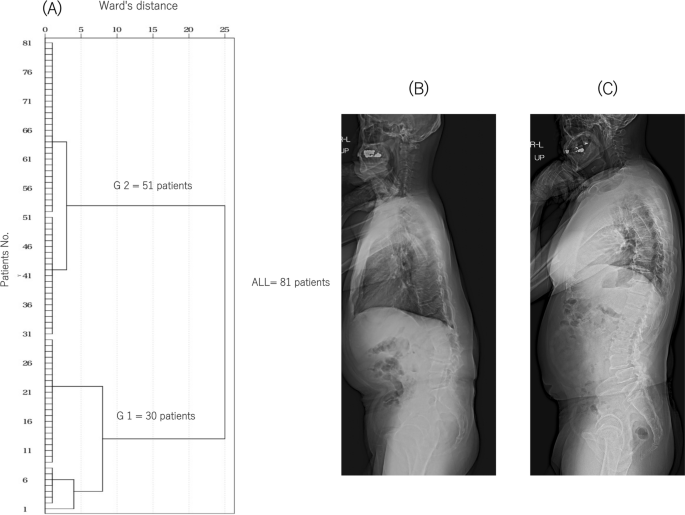

Cluster analysis was performed using the hierarchical cluster analysis procedure using IBM SPSS Statistics (version 23.0; IBM Corp., Armonk, NY, USA). Cluster analysis was used to classify the patients into two groups based on the preoperative SVA (Fig. 2): group 1 with a high SVA (129.0 ± 53.4 mm) and group 2 with an SVA close to normal (30.8 ± 23.5 mm).

Dendrograms of the hierarchical classification of patients who received LLIF surgery (n = 81). (A) The numbers of patients in each cluster at different Ward’s distances are shown. The patients were classified into groups 1 (n = 30) and 2 (n = 51) from the cluster analysis. Standing full-length X-ray lateral views of typical cases in groups 1 (B) and 2 (C).